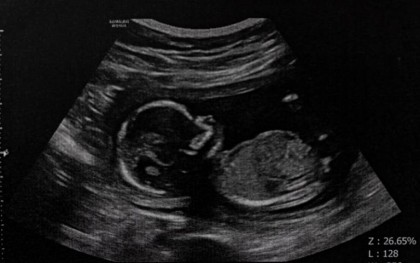

Pentru a ajunge la aceste concluzii, cercetătorii au analizat rezultatele pentru 123 de femei care au furnizat mostre de sânge și au avut examinări ecografice regulate ale dimensiunii și stării de bine a bebelușilor lor. Inițial, au măsurat nivelurile a 102 proteine din mostrele de sânge de la 63 de femei și au combinat aceste date cu măsurătorile ecografice pentru a construi modele statistice care să poată prezice rezultatele sarcinii. Aceste modele au fost apoi validate folosind măsurători de la alte 60 de femei din cohorta studiului.

Dr. Spencer a menționat că, prin evaluarea atât a măsurătorilor ecografice, cât și a nivelurilor de proteine, au reușit să prezică care sarcini vor rezulta în naștere moartă sau deces neonatal și care ar putea necesita naștere extrem de prematură înainte de 28 de săptămâni de sarcină.